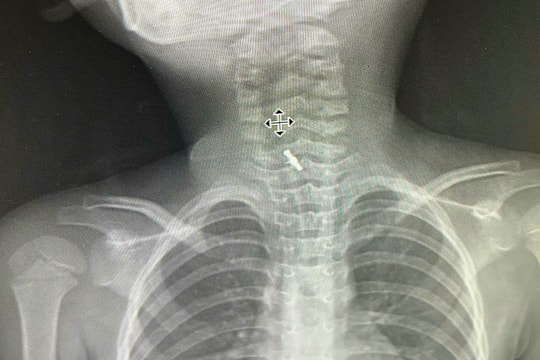

Cứu sống bệnh nhân bị đinh thép xuyên khí quản

08/08/2025 07:49

Mới đây, tại Khoa Cấp cứu - Bệnh viện Trung ương Quân đội 108, tiếp nhận một ca vết thương khí quản xuyên thấu hiếm gặp, tổn thương phức tạp, đe dọa trực tiếp đến tính mạng người bệnh.